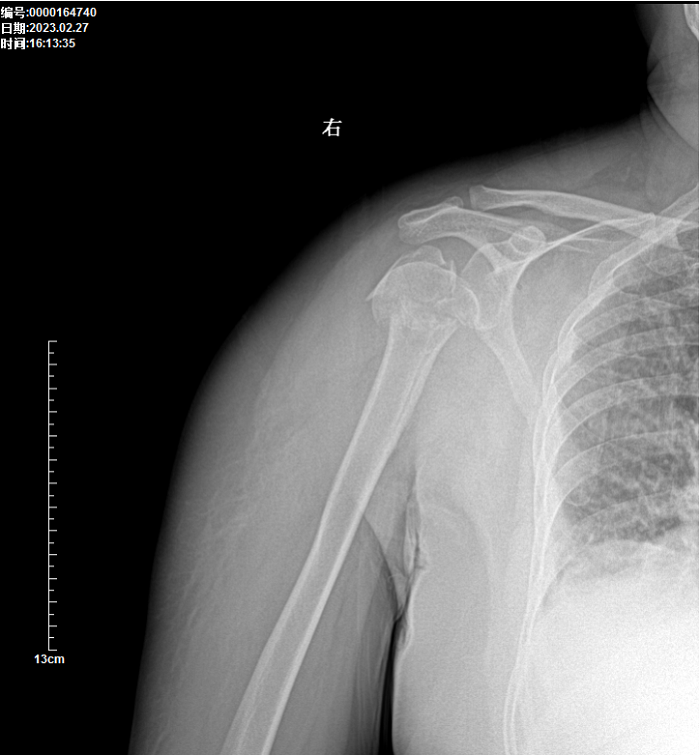

据悉,该名患者是一位68岁老年女性,因不慎摔倒致伤右肩部,伤后疼痛剧烈,右上肢活动障碍,遂到我院骨科就诊。入院后完善相关检查,诊断为:右侧肱骨近端粉碎性骨折Neer IV型,右侧肱骨头脱位,重度骨质疏松症。由于患者肱骨近端粉碎性骨折,肱骨头碎裂严重,若行常规的钛板内固定手术,可能复位不理想,后期出现创伤性关节炎可能性较大,将来有发生肱骨头缺血性坏死的可能,肩关节活动障碍的几率较大。

鉴于患者既往身体素质较好,为确保以后的生活质量,经过全科医师反复讨论,决定行右肩关节置换手术,尽可能减少骨折后遗症,最大限度恢复肩关节功能。确定手术方案后,经过周密的术前设计和准备,在麻醉科和骨科医护人员的密切配合下,顺利为患者实施手术。术后X片、CT复查显示假体位置良好,对位对线准确,松紧度适宜。目前患者能在医师指导下逐步进行康复锻炼,肩关节活动明显改善,患者对手术十分满意。经过康复训练,患者右上肢功能也将逐步恢复到健肢水平。